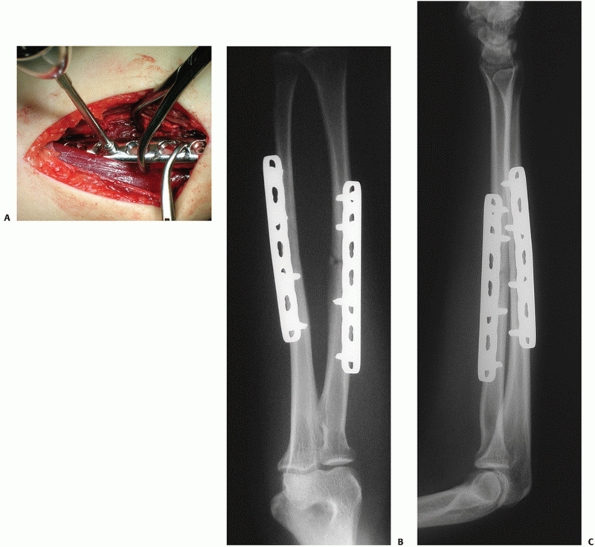

Although the LCP (Fig. 31-12) represents the

latest development in plate development, its usage in fractures with

simple configuration and its superiority over conventional plating

systems (e.g., LC-DCP) has yet to be proven.

|  |

| FIGURE 31-12 Fracture of the forearm treated with a locking compression plate. A. The application of locking screw. Good alignment and uneventful healing was seen in the anteroposterior (B) and lateral (C) follow-up radiographs at 6 months. |